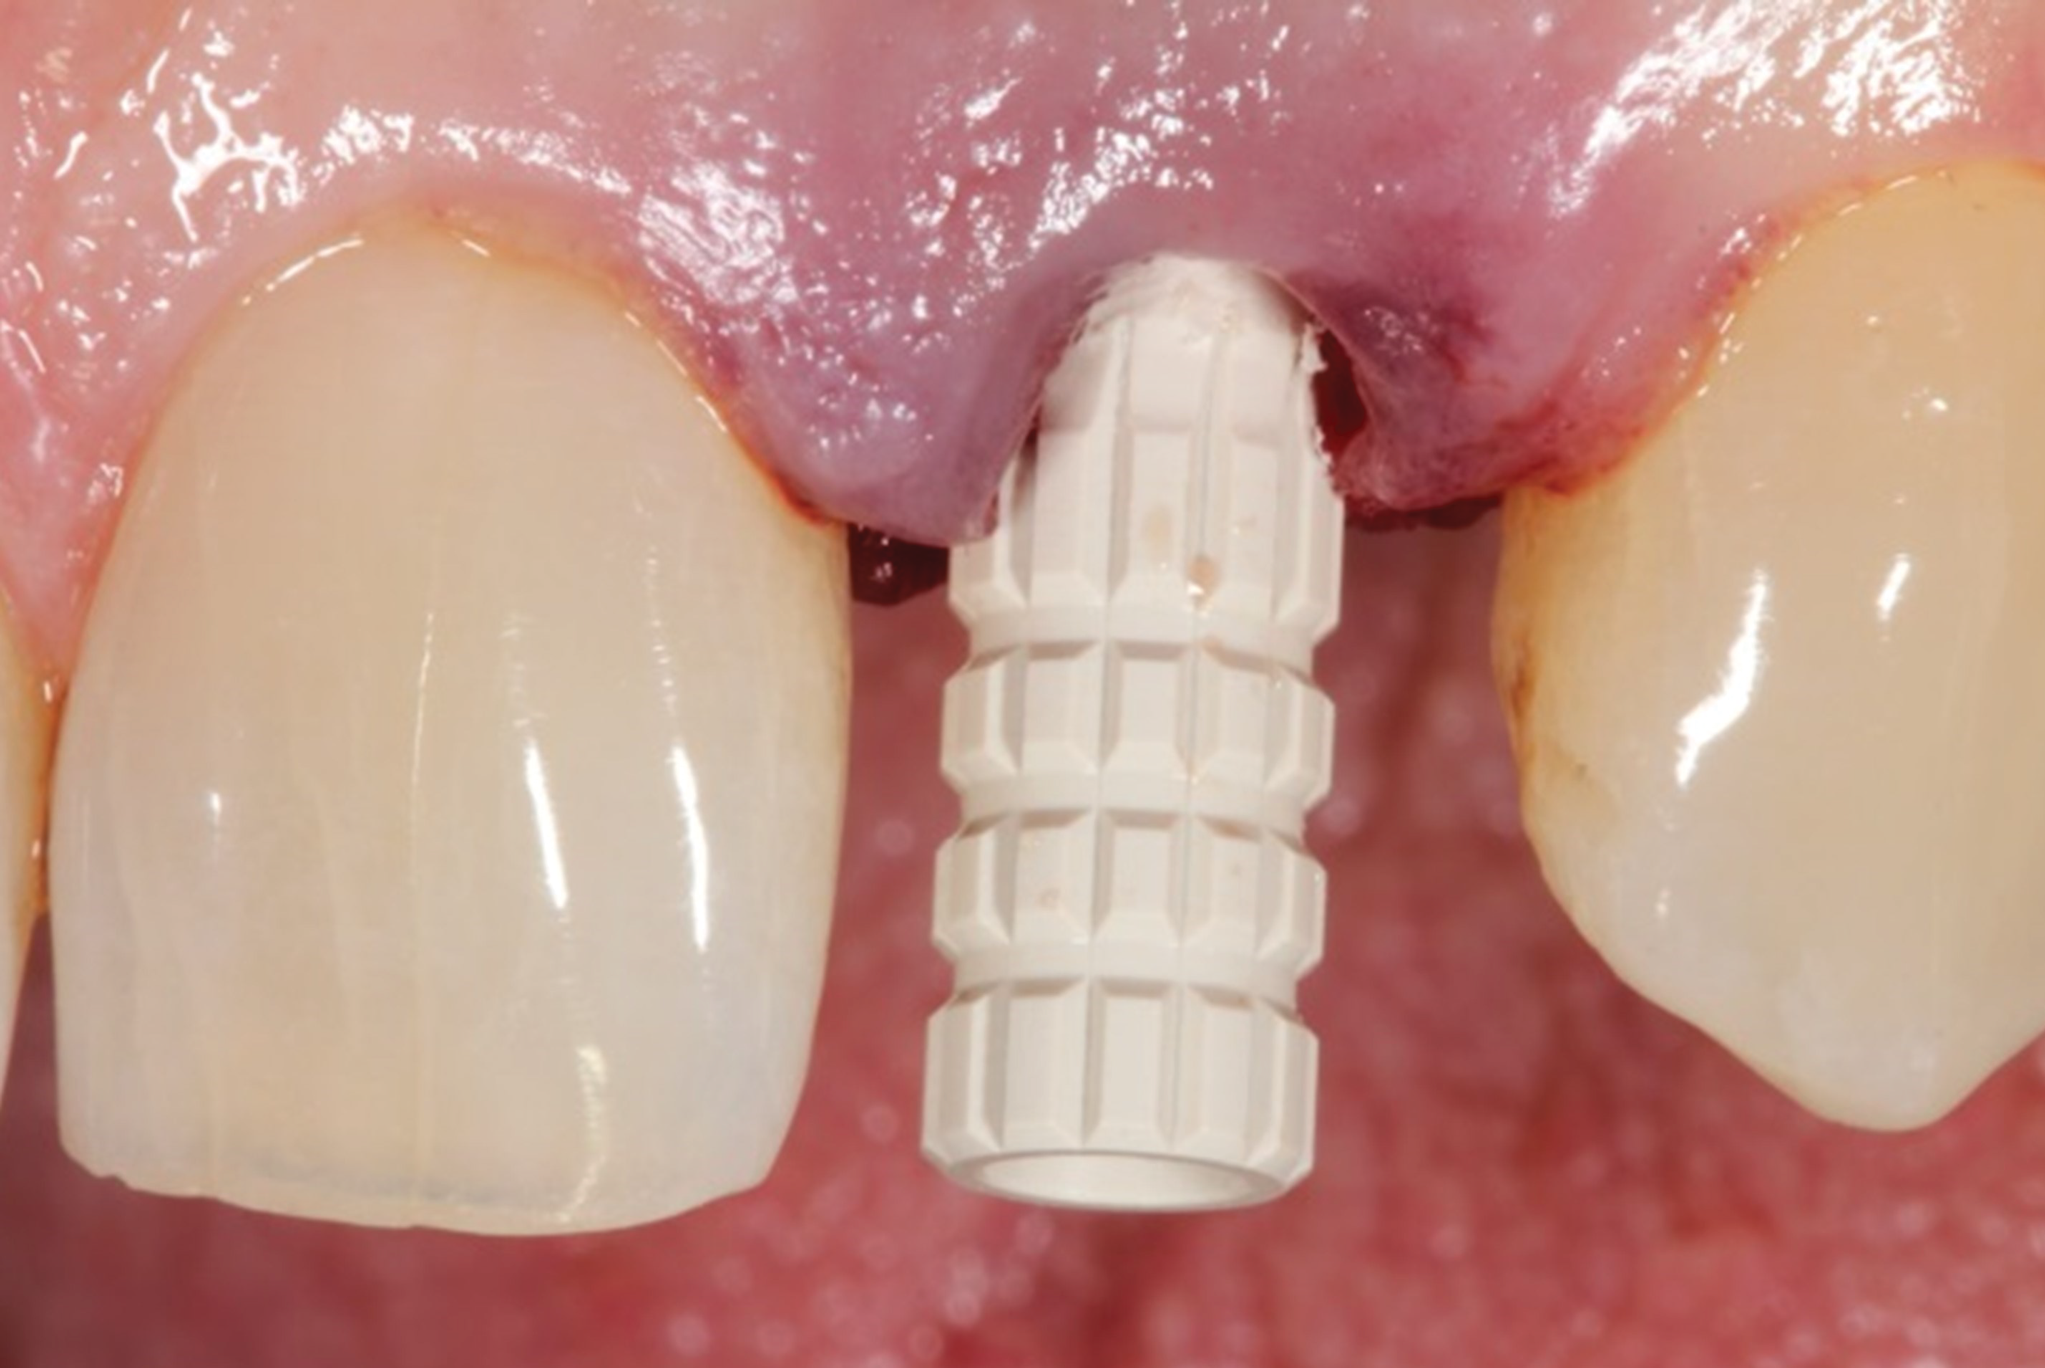

Fig 8. A PEEK temporary abutment is seated.

Figure 8

Fig 9. A polycarbonate facial shell is luted to the temporary abutment with acrylic extraorally. A prefabricated crown form should be chosen with appropriate dimensions for the space. Acrylic will be added to the proximal and palatal surface to establish proper tooth form, contact points, and occlusal scheme, and the cylinder reduced for adequate interocclusal space.

Figure 9